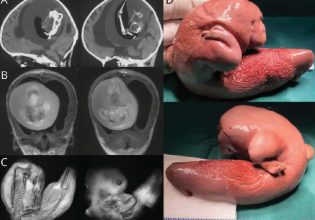

Συγκλονιστικές εικόνες έκαναν το γύρο του κόσμου: ένας πατέρας να σφίγγει το χέρι της 15χρονης κόρης του που είναι θαμμένη κάτω από τα συντρίμμια στην Τουρκία· ή αυτή ενός νεογέννητου που διασώθηκε στη Συρία ενώ ήταν ακόμη ενωμένο με τον ομφάλιο λώρο με τη νεκρή μητέρα του.